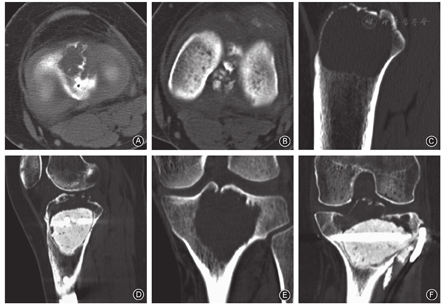

本组1例膝关节腔内色素沉着绒毛结节性滑膜炎患者,关节镜术后3年出现复发,CT扫描示胫骨近端近髁间隆突处骨质破坏,MRI示胫骨近端近髁间隆突处肿瘤占位,与关节腔交界处存在"瘤蒂",第2次关节腔切开清理术前,向关节腔注入碘海醇,"C"型臂X线机透视造影剂自隆突中凹部孔道所在位置向胫骨近端瘤腔渗入(图5)。

1例胫骨近端骨巨细胞瘤,患者术前CT扫描示瘤腔与"胫骨髁间隆突孔"相通,行刮除植骨+骨水泥填充术,术后6个月复发,复发后CT扫描示肿瘤由髁间突入关节腔(图6)。